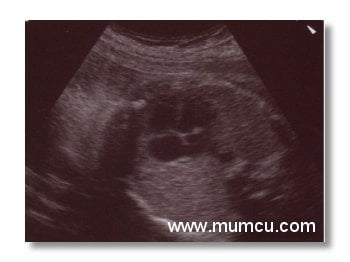

8 haftalık gebelikte amniyon kesesi, yolk kesesi ve embryo

Vajinal ultrasonografi